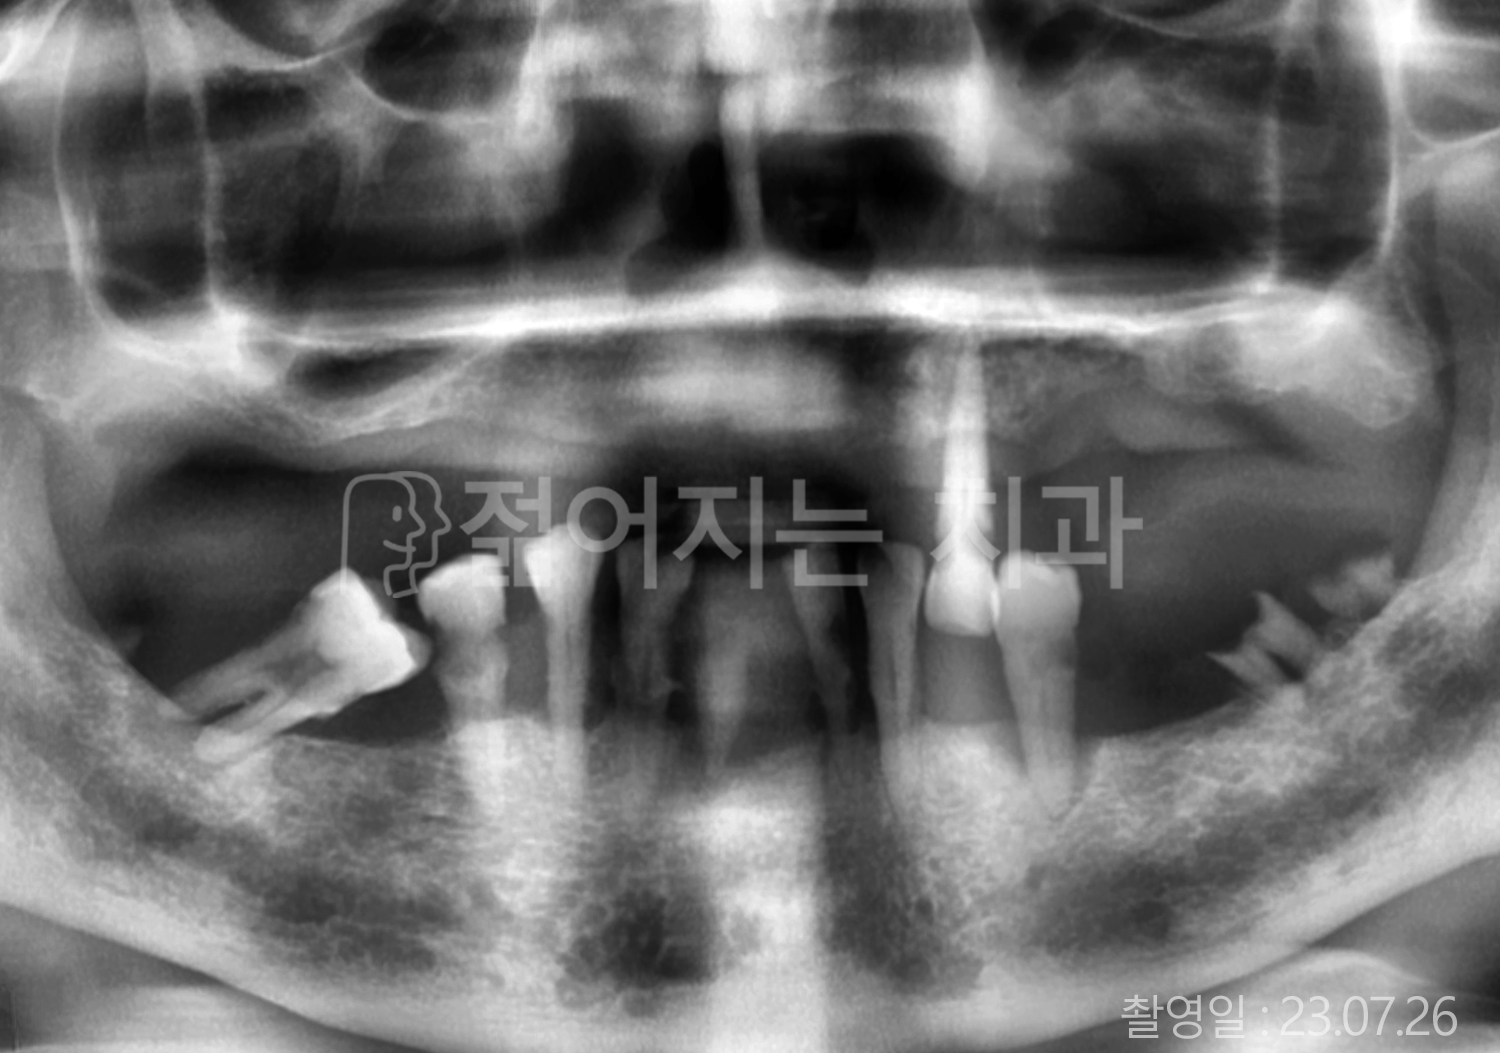

• 60대 전체치아 10개 이상 임플란트